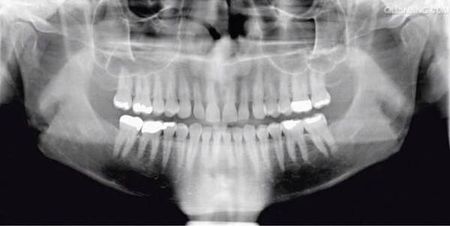

2)全景X牙片

全景X線片(panoramic X-ray film)是口腔頜面影像學(xué)特有的一種檢查方法,是曲面體層攝影技術(shù)和口腔頜面部的改良應(yīng)用。X線球管沿成弧形的上下頜骨旋轉(zhuǎn),成像不重疊。一次曝光即可將全口牙及雙側(cè)上、下頜骨、上頜竇及顳下關(guān)節(jié)等部位的體層影像顯示于一張膠片上。常用于口腔頜面部腫瘤,外傷及頜骨畸形的檢查。